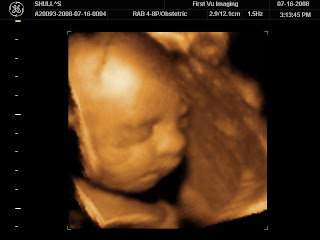

Look at our baby!

Thanks to Andrea, Andrew and I went to have 4-D photos taken of our baby. It was such a fun experience. The technician was careful to only snap photos from the waist up so that we didn’t find out the gender. The baby behaved very well during the session. It had a fascination with one of its feet. It had the little foot all the way up by the head playing with it and wiggling it around. It’s hard to believe that in 2 months, this precious little baby will be at home with us.